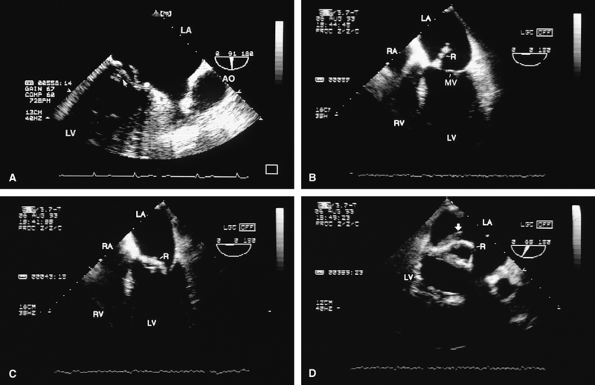

FIGURE 5.1. St. Jude mitral prosthesis: normal. The mitral prosthesis (MP) is seen in the closed (A) and open (B) positions. A. Prosthetic reverberations or artifacts (arrows) that clutter the left ventricle (LV). B. The two leaflets (1 and 2) of the prosthesis in the open position together with the reverberations. C. Aliased diastolic inflow into the LV is seen with a small region of flow acceleration. D–G. Two to three small jets of mitral regurgitation (MR; arrows) are shown. These are normal findings. Usually, these jets are narrow and do not show significant turbulence but may extend deep into the left atrium (LA). G. illustrates the norm (not pansystolic). H. Small linear echoes are normally seen on both the atrial and ventricular aspects of the prosthesis and represent suture material. I, J. Immediately postsurgery, although the patient is still on partial bypass, one leaflet of the prosthesis (P) may intermittently fail to open. This should not be mistaken for dysfunction. When cardiac output improves, normal opening of both leaflets occurs consistently. RV, right ventricle; RA, right atrium. |